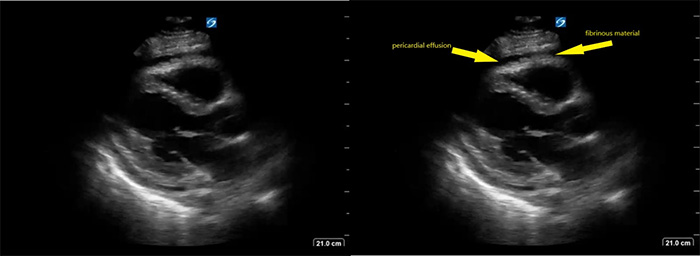

- Pericardial effusion that may or may not contain fibrinous debris: OR = 2.821

Figure 5. Parasternal long axis view of heart with fibrinous pericardial effusion

Video 7. Parasternal long axis view of heart with fibrinous pericardial effusion

- In one study of patients with HIV and large pericardial effusions, 69.5% had EPTB as a cause of the effusion.22